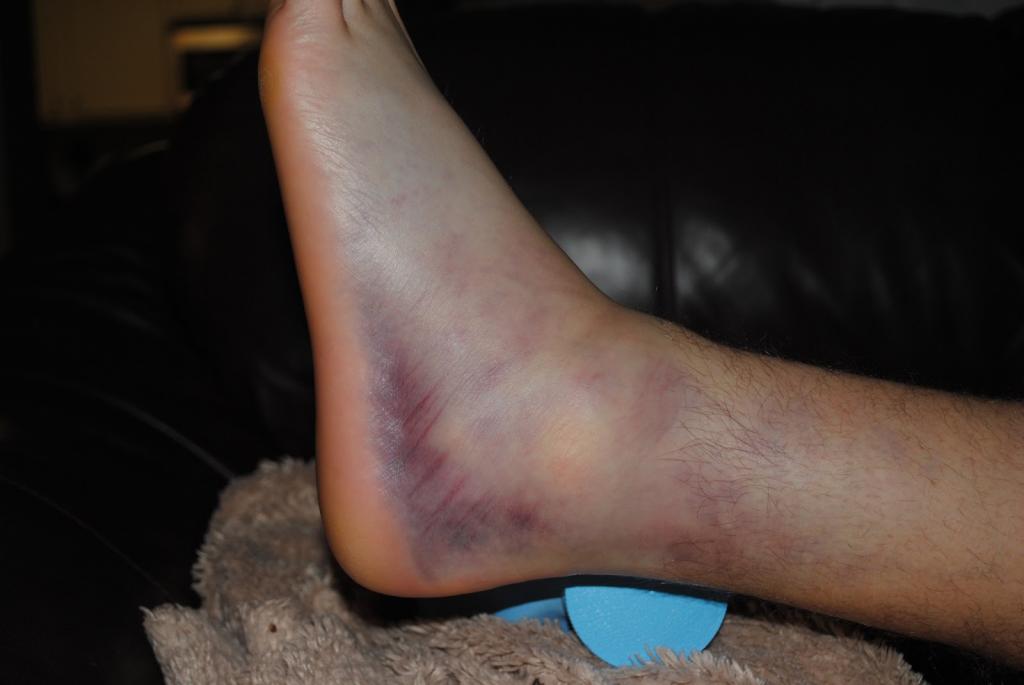

Для 2 и 3 степени растяжения связок голеностопного сустава характерны следующие симптомы:

- Выраженная боль. Она появляется сразу же после получения травмы, а по своей выраженности может превышать даже перелом костных структур. Самая сильная боль сохраняется первый час, затем ее выраженность немного ослабевает. Если же попытаться наступить на пораженную конечность, она снова станет нестерпимой. Одним из факторов, вызывающим боль, является отек. По мере своего распространения он оказывает давление на сосуды и нервные окончания.

- Отек. Это основной признак, свидетельствующий о растяжении голеностопного сустава. При этом он никогда не распространяется на всю стопу или даже голень. Он сохраняется в течение примерно 7 суток, затем начинает рассасываться, а на его месте образуется гематома.

- Синяк. Примерно через 6-7 дней после получения травмы он появляется и распространяется на область всей лодыжки с пораженной стороны. Через несколько недель гематома начинает спускаться в самый низ — к подошвенной зоне. На протяжении всего этого времени синяк меняет свой цвет от ярко-синего до желтого.

- Отсутствие возможности передвигаться самостоятельно. В первые несколько дней человек не может даже наступить на пораженную конечность.